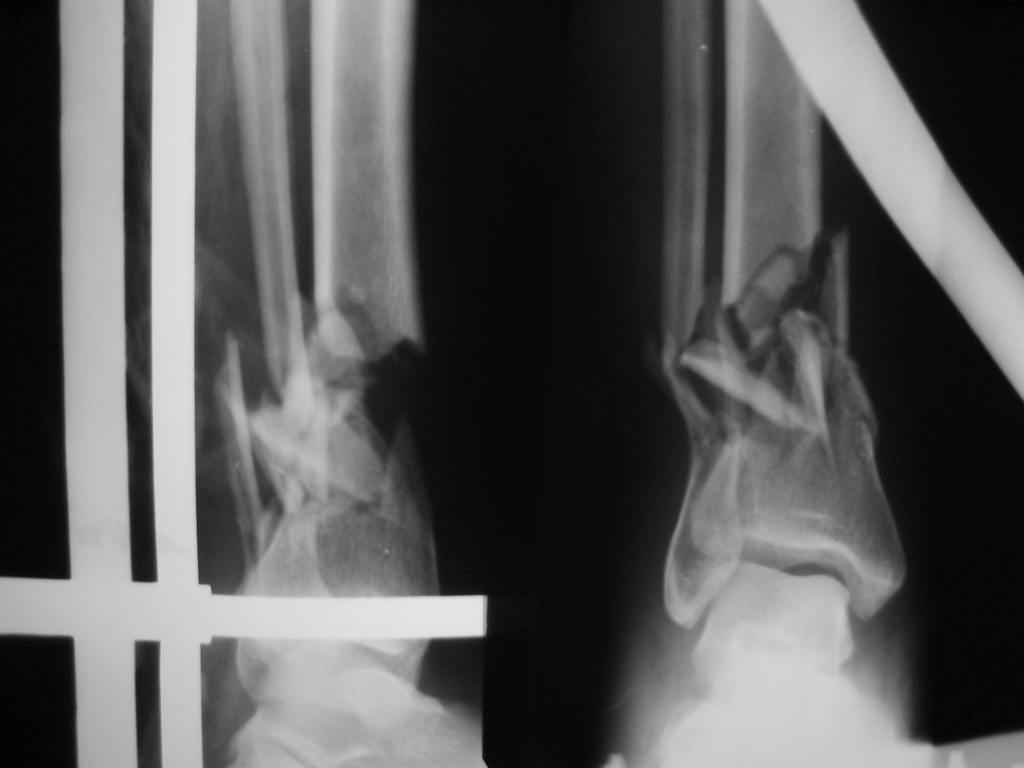

Открытый перелом (1А Каплан)у женщины 39 лет - падение плиты на голень.

Выбран вариант:ДРУ на месяц и EXPERT.С частичной нагрузкой на конечность сразу после операции.Хотелось бы услышать мнения по этому случаю.

Непонятна такая отсрочка. Почему не через 7-10 дней? И снимок показан не в аппарате, а на вытяжении. Если при поступлении не наложили аппарат, получится 2 раза в операционную брать?

Если по каким-то для меня неочевидным, но на месте видимым веским причинам планируется аппарат на месяц - двумя спицами лучше не ограничиваться, а наложить что-то посерьезнее, сделать нормальный гибридный аппарат.